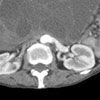

Figure 2

White blood cell count is 17,130/µL, with 82% polymorphonuclear leukocytes; hemoglobin level is 7 g/dL; platelet count is 538,000/µL; prothrombin time is 16.7 seconds; and partial thromboplastin time is 24.3 seconds. Electrolyte levels and renal and liver function test results are normal. A scout film and CT scan of the abdomen are shown.

Mucinous cystadenoma

The CT scan showed a large complex mass, suggestive of ovarian origin, that filled the entire pelvis and extended into the abdomen. Further tests revealed a cancer antigen (CA) 19-9 level of 2568 U/mL, a CA 125 level of 172 U/mL, and a carcinoembryonic antigen (CEA) level of 23.6 ng/mL.